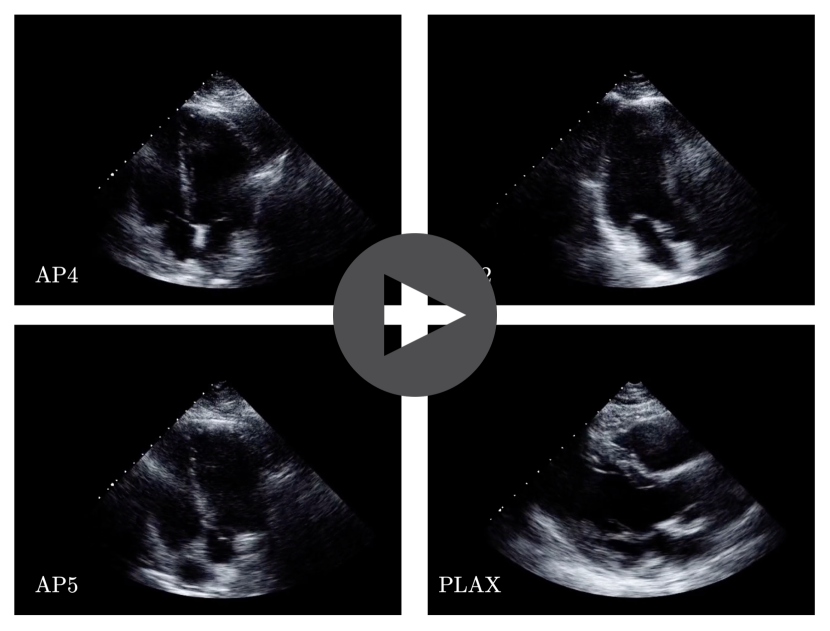

In  Figure 9,  Figure 10, and  Figure 11, we show a screenshot of synced cines captured from different views along with their trajectories in the embedding space. Please refer to the supplementary files to see the videos. In synced videos, note the fine-grained synchronization that in some time points, frames are dropped or repeated to make the movements of valves and walls be aligned between the cines. In  Figure 12, a snapshot of a video from four synced cines can be observed. In this example, the generalizibility of the method even in the views not found in the training set can be observed.

Refer to caption

Figure 12: A screenshot of synced cines captured from AP4, AP2, AP5, and PLAX views.